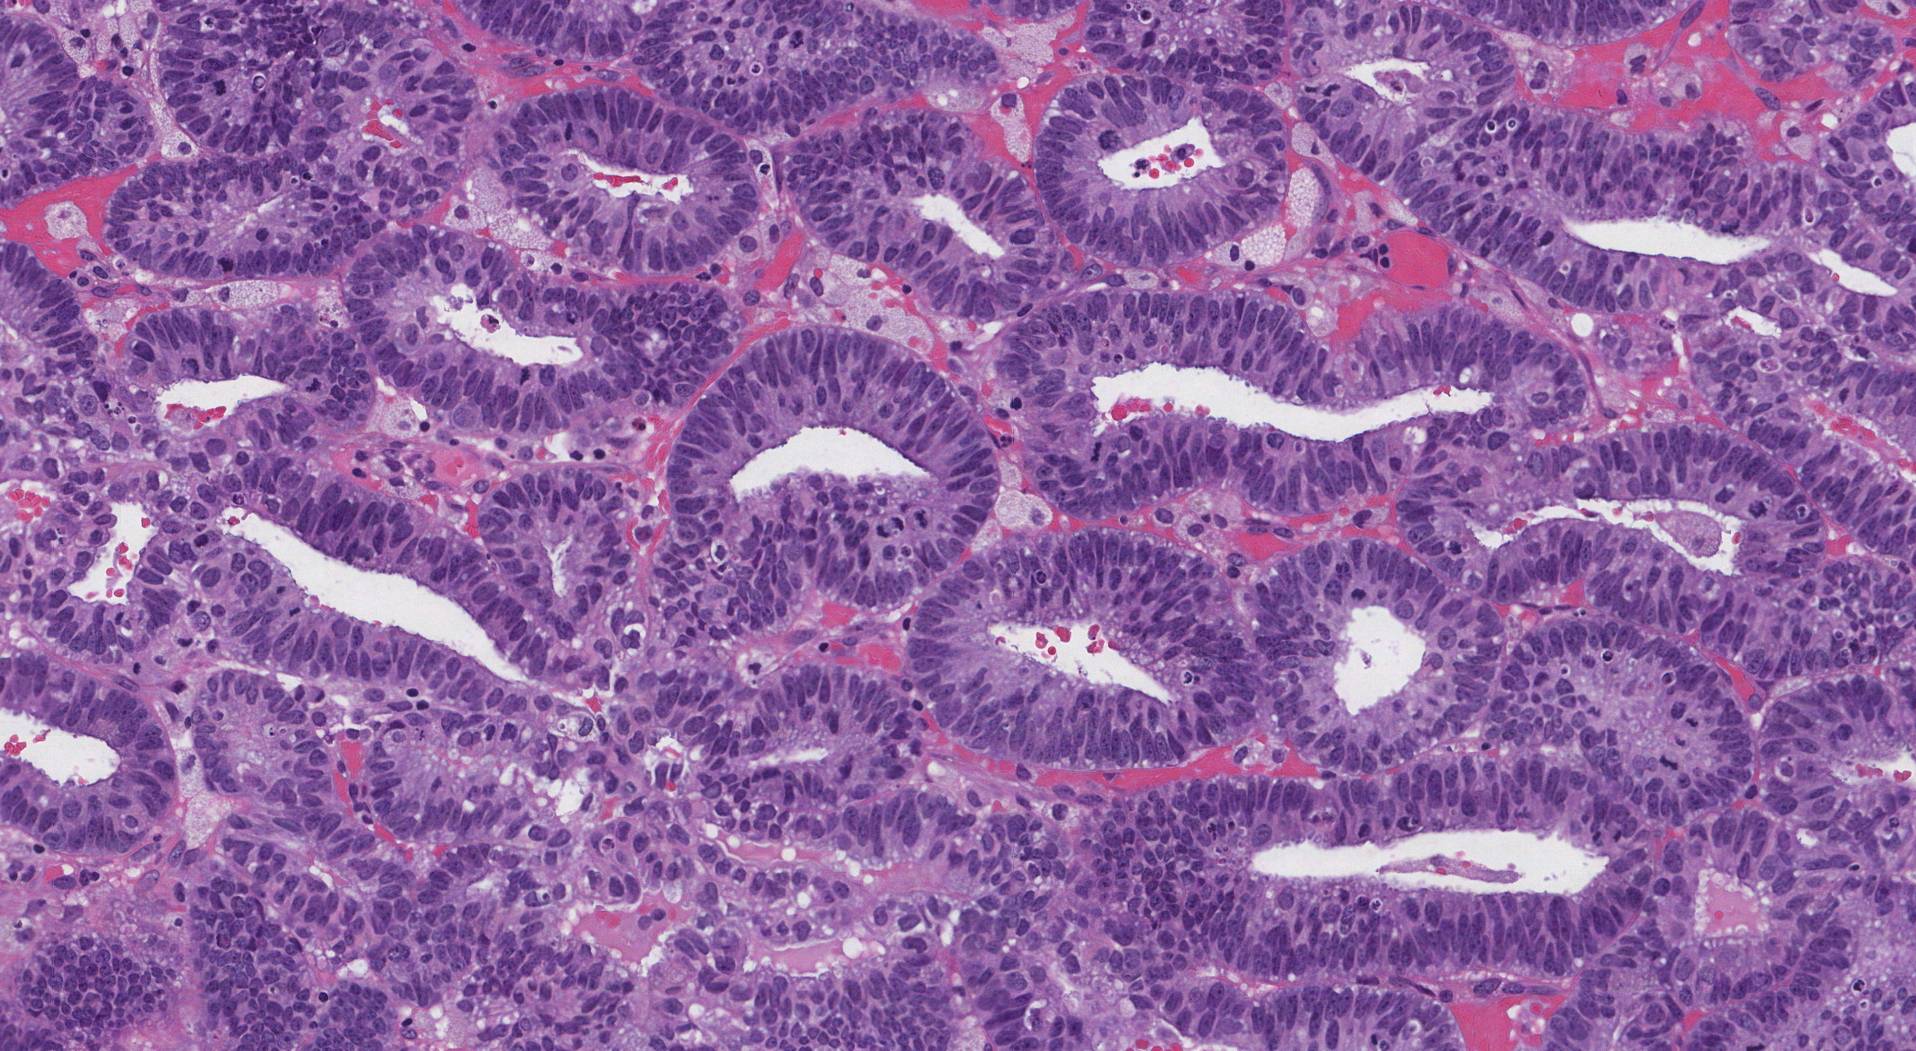

Endometrioid intraepithelial neoplasia (EIN)